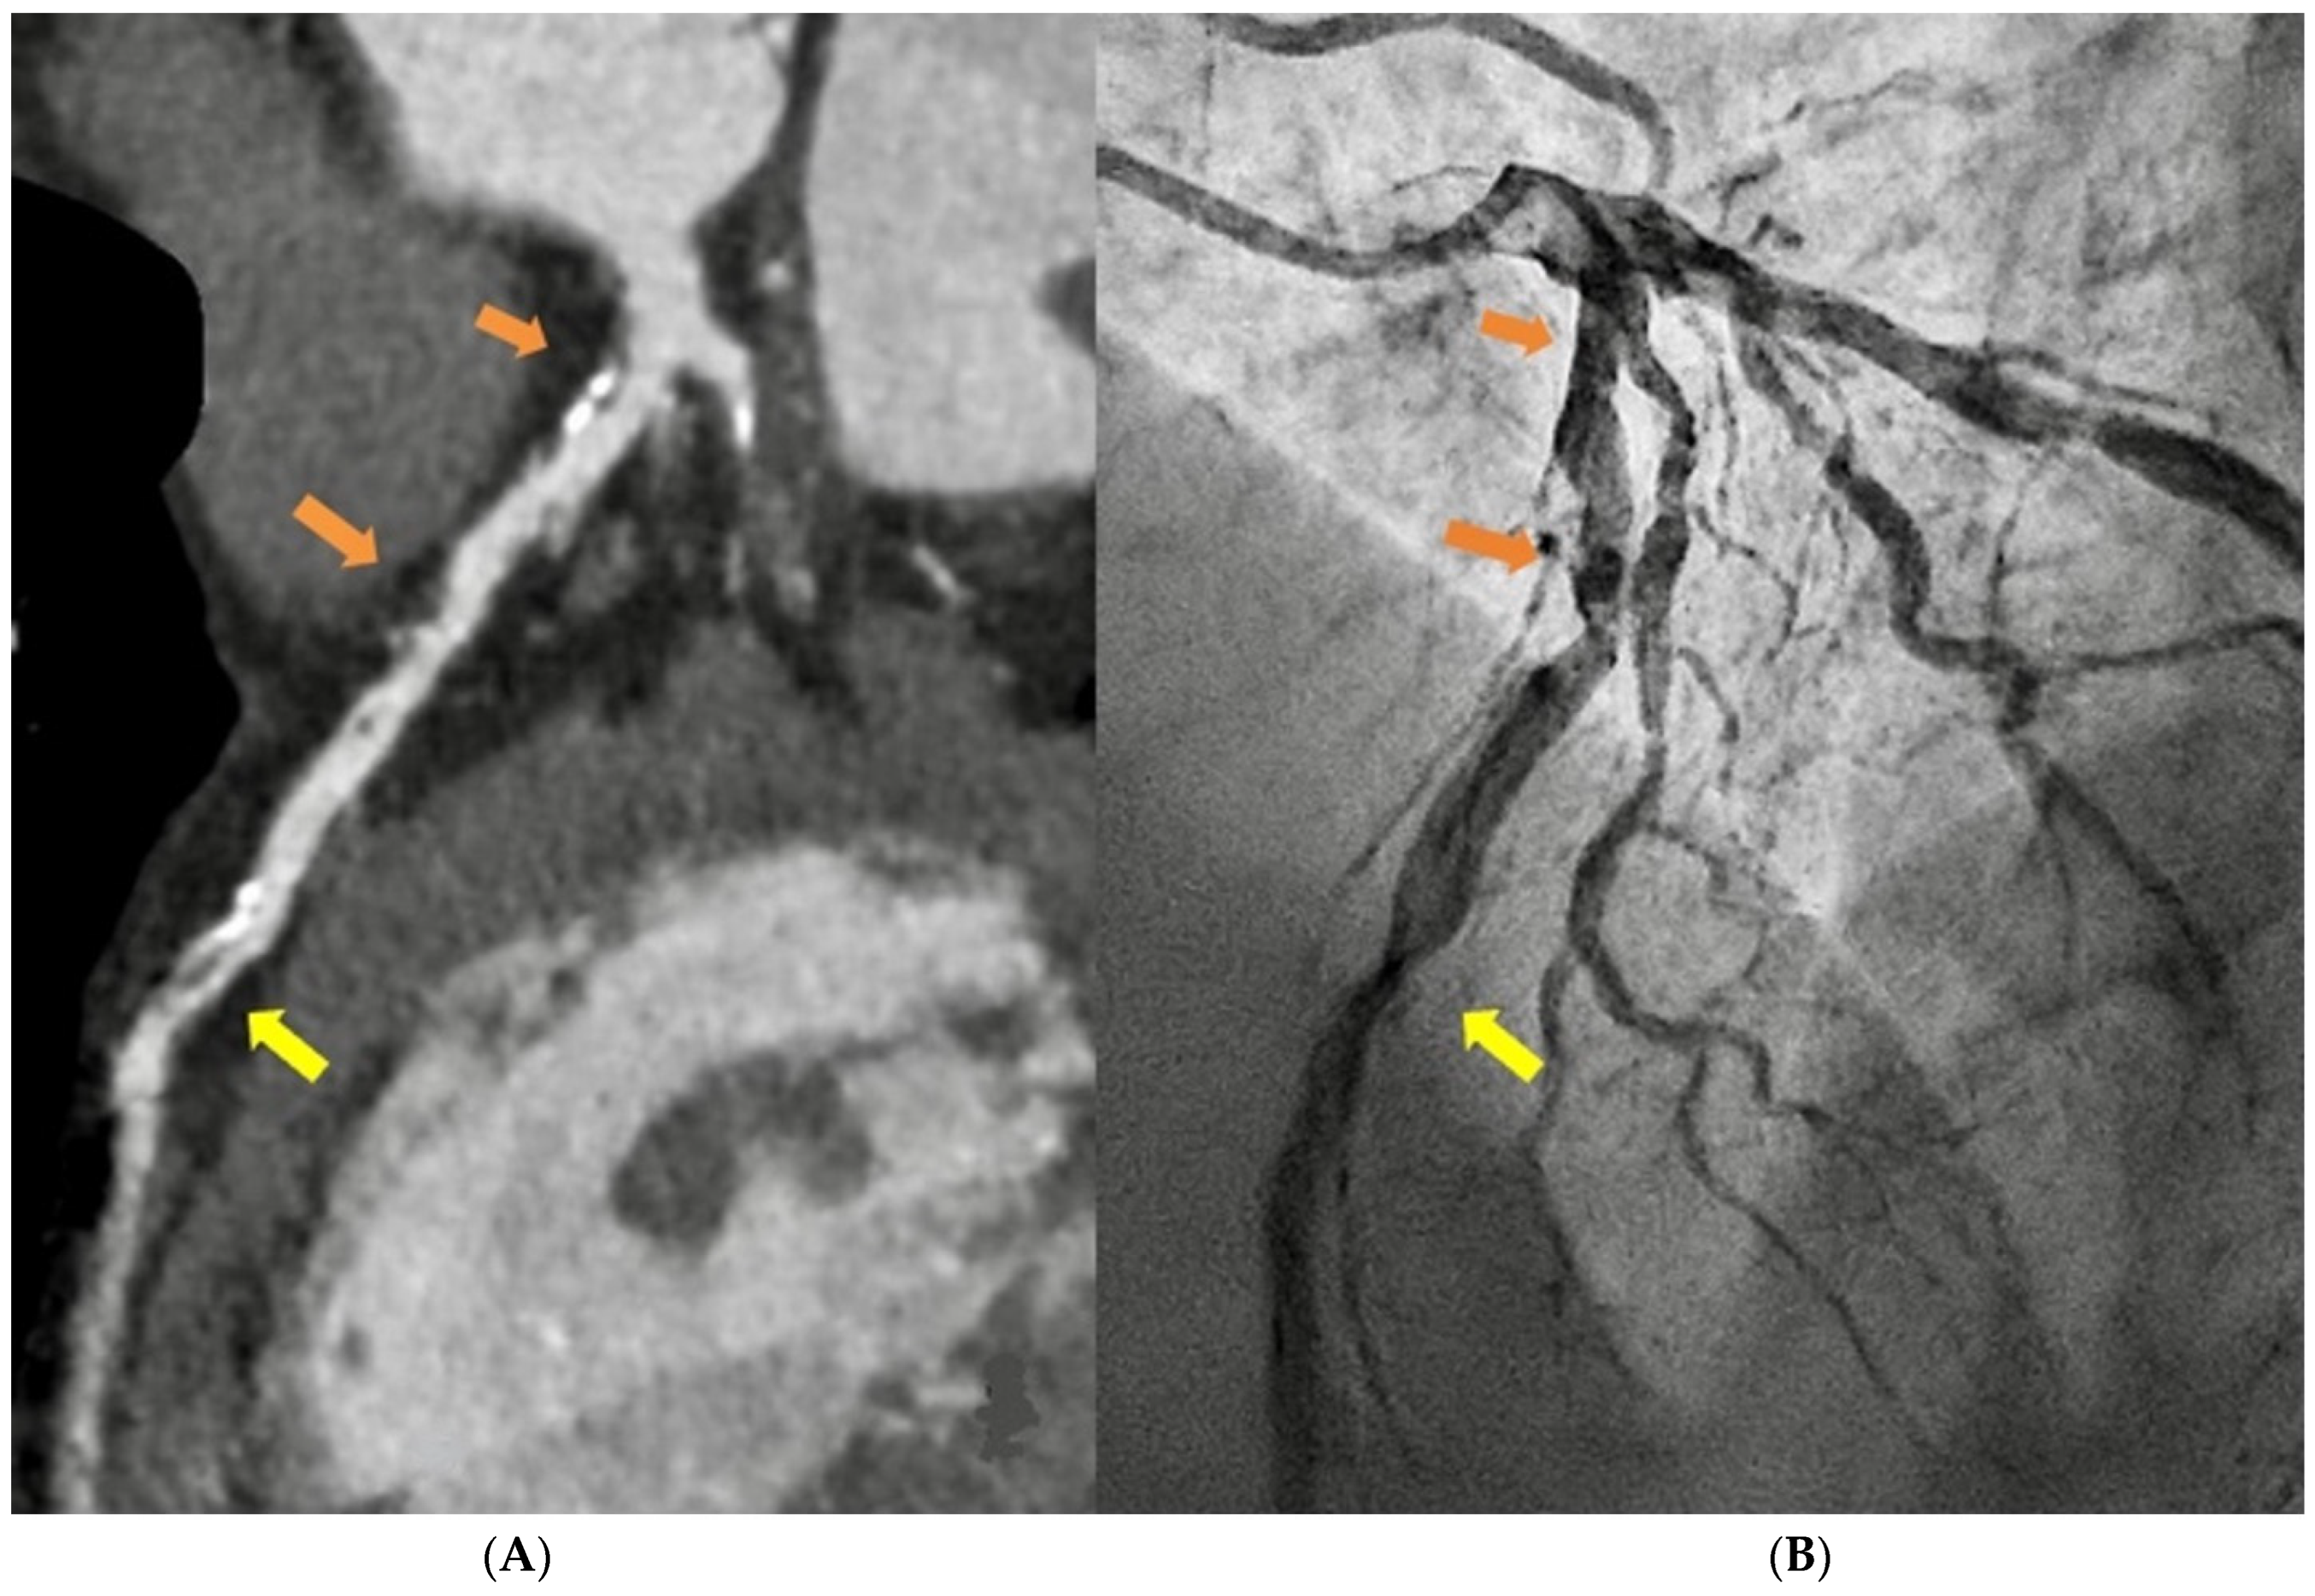

1.1. Computed Tomography

- Cademartiri, F.; Casolo, G.; Clemente, A.; Seitun, S.; Mantini, C.; Bossone, E.; Saba, L.; Sverzellati, N.; Nistri, S.; Punzo, B.; et al. Coronary CT angiography: A guide to examination, interpretation, and clinical indications. Expert Rev. Cardiovasc. Ther. 2021, 19, 413–425. [Google Scholar] [CrossRef]

- Cury, R.C.; Leipsic, J.; Abbara, S.; Achenbach, S.; Berman, D.; Bittencourt, M.; Budoff, M.; Chinnaiyan, K.; Choi, A.D.; Ghoshhajra, B.; et al. CAD-RADSTM 2.0—2022 Coronary Artery Disease-Reporting and Data System. J. Cardiovasc. Comput. Tomogr. 2022, 16, 536–557. [Google Scholar] [CrossRef]

- Ferencik, M.; Mayrhofer, T.; Bittner, D.O.; Emami, H.; Puchner, S.B.; Lu, M.T.; Meyersohn, N.M.; Ivanov, A.V.; Adami, E.C.; Patel, M.R.; et al. Use of High-Risk Coronary Atherosclerotic Plaque Detection for Risk Stratification of Patients With Stable Chest Pain. JAMA Cardiol. 2018, 3, 144. [Google Scholar] [CrossRef]

- Oikonomou, E.K.; Marwan, M.; Desai, M.Y.; Mancio, J.; Alashi, A.; Hutt Centeno, E.; Thomas, S.; Herdman, L.; Kotanidis, C.P.; Thomas, K.E.; et al. Non-invasive detection of coronary inflammation using computed tomography and prediction of residual cardiovascular risk (the CRISP CT study): A post-hoc analysis of prospective outcome data. Lancet 2018, 392, 929–939. [Google Scholar] [CrossRef]